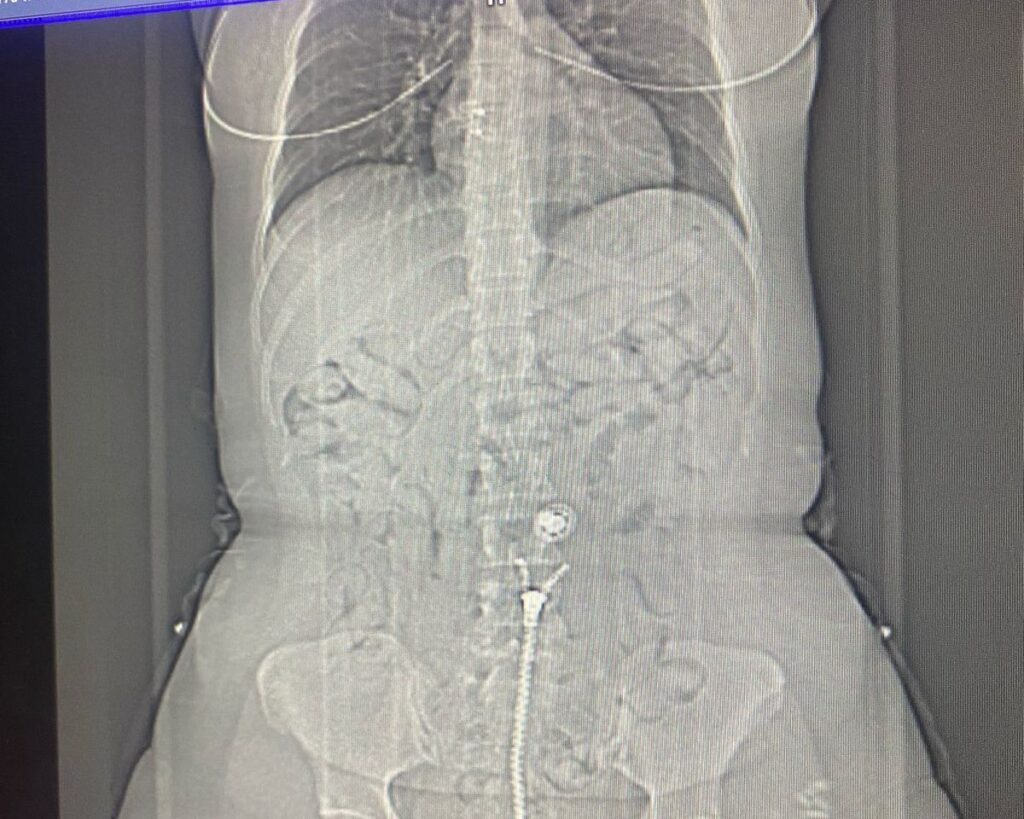

A mulher também confessou aos agentes que estava transportando a droga no estômago e que havia engolido cerca de 80 cápsulas da droga. O caso ocorreu por volta de 00h30 e a mulher foi levada ao hospital.

A brasileira foi encaminhada ao Hospital Metropolitano de Belém, onde foram feitos exames e os profissionais precisaram expelir as demais cápsulas. Além disso, uma quantia de 500 euros foi apreendido em posse da suspeita.